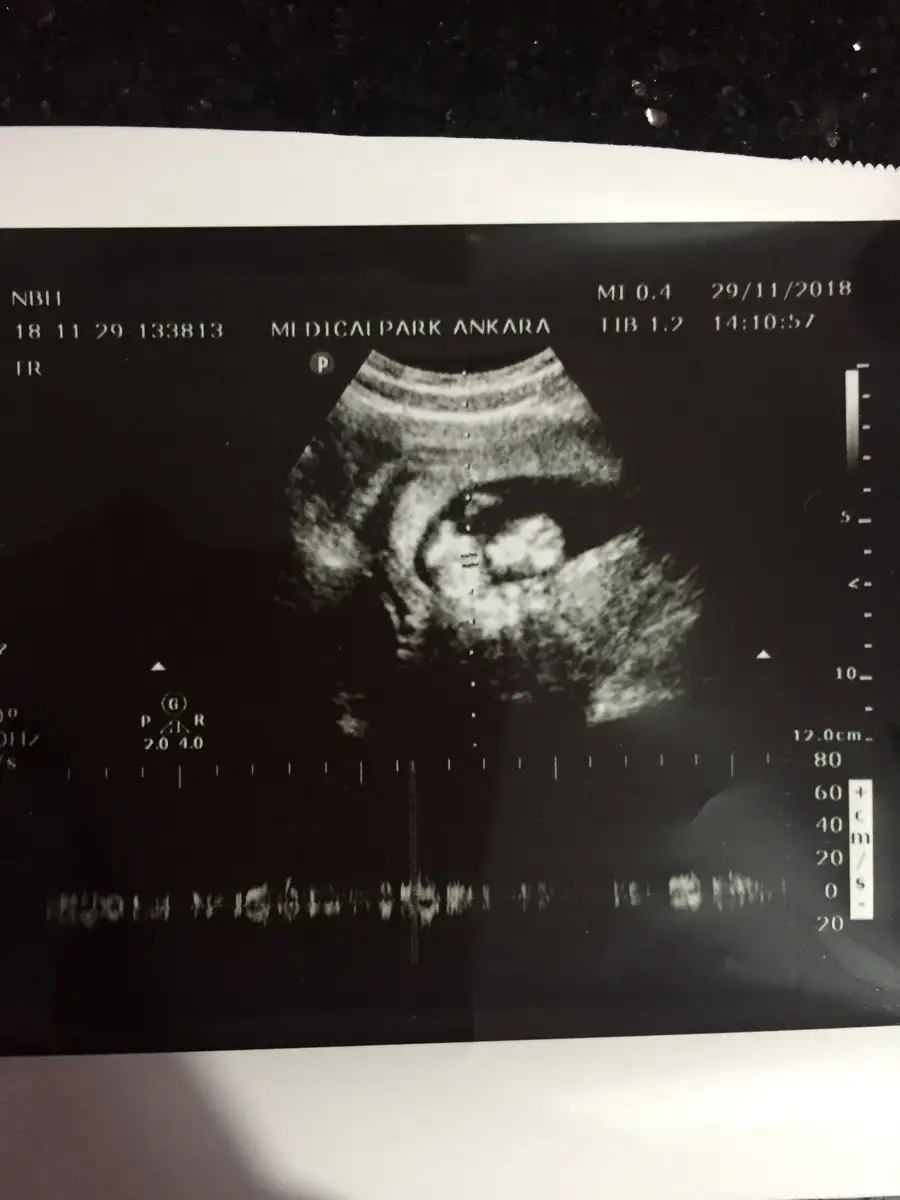

Ay maşallah erkekler çoğunlukta dedik kız haberleri de almaya başladık prenseslerimiz de çoğalıyorwiha02 @minnosu kızlar geldim şimdi. Bebişim gayet sağlıklı 6.52 olmuş boyu. Doktor muhtemelen kız dedi. İdrar verdim pazartesi çıkacak dediler. İkili sonucu grafik çıkması lazım onu alıp gelin dedi pazartesi onuda hallederim sonuçlar için tekrar gideceğim. Bu arada ben bugün işe gitmemiştim birde rapor yazdı. Eklemlerim ağrıyor normal mi diye sordum evet dedi. Benden haberler bukadar